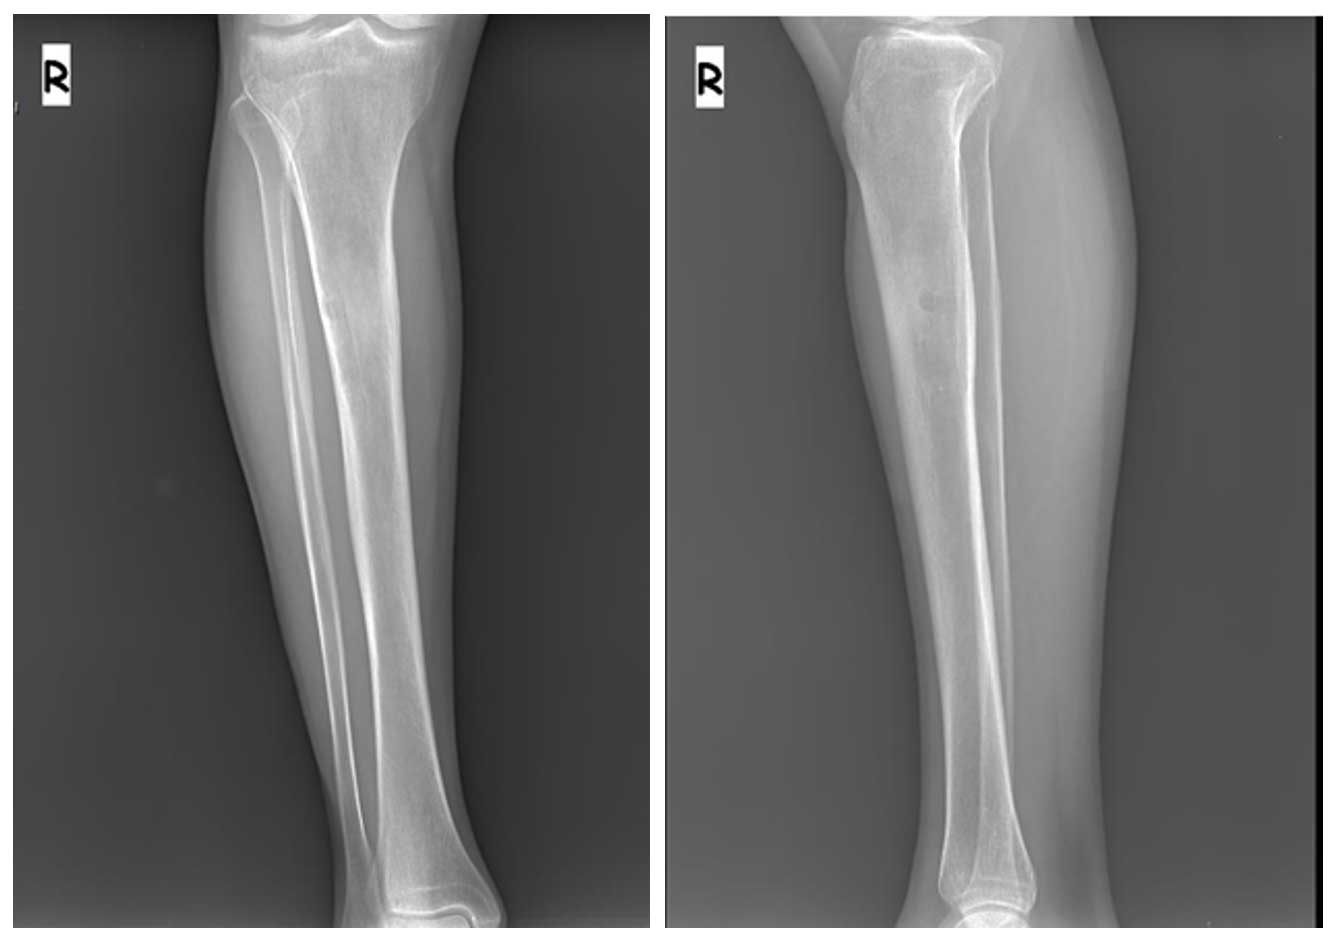

Ameliyat Öncesi: Röntgende proksimal tibiada litik sklerotik kitle görünmekte.